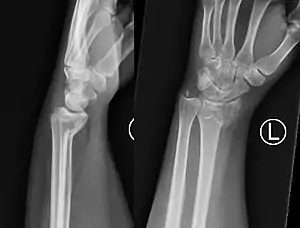

Two views should be obtained: AP and lateral.

PA radiography will look very similar to a Colles' fracture, with a fracture along the distal metaphysis of the radius (can be shortened or comminuted). Lateral radiography will demonstrate volar angulation / displacement of the fracture.[7]